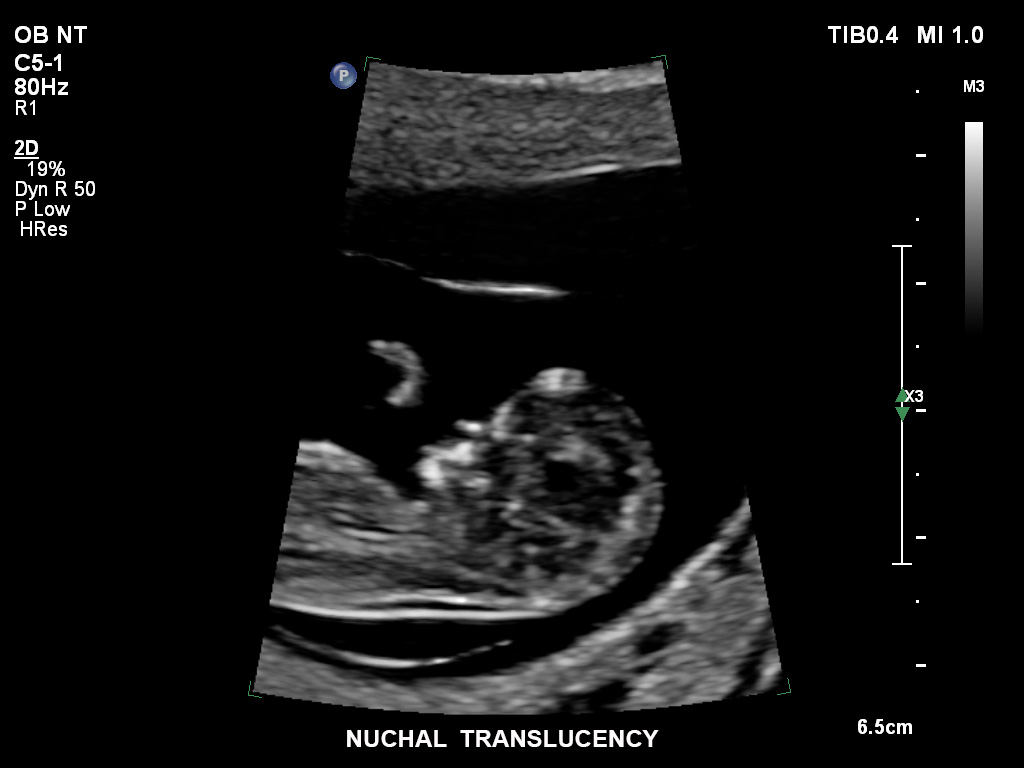

• C9-2 PureWave-Breitband-Convex-Schallkopf für Hochfrequenz-Bildgebung in der Gynäkologie und der Geburtshilfe, insbesondere für die Untersuchung im Hinblick auf mögliche Anomalien im ersten Schwangerschaftstrimester

• C10-3v PureWave-Breitband-Endo-Convex-Schallkopf, ideal für anspruchsvolle Myom- und komplexe Ovar-Untersuchungen sowie Bildgebung im ersten Schwangerschaftstrimester